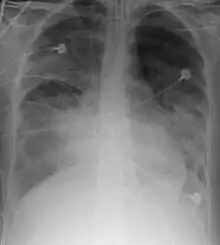

X-ray

A chest X-ray showing right sided (seen on the left of the picture) pulmonary contusion associated with rib fractures and subcutaneous emphysema

Chest X-ray is the most common method used for diagnosis,[37] and may be used to confirm a diagnosis already made using clinical signs.[20] Consolidated areas appear white on an X-ray film.[42] Contusion is not typically restricted by the anatomical boundaries of the lobes or segments of the lung.[27][43][44] The X-ray appearance of pulmonary contusion is similar to that of aspiration,[32] and the presence of hemothorax or pneumothorax may obscure the contusion on a radiograph.[25] Signs of contusion that progress after 48 hours post-injury are likely to be actually due to aspiration, pneumonia, or ARDS.[10]

Although chest radiography is an important part of the diagnosis, it is often not sensitive enough to detect the condition early after the injury.[35] In a third of cases, pulmonary contusion is not visible on the first chest radiograph performed.[7] It takes an average of six hours for the characteristic white regions to show up on a chest X-ray, and the contusion may not become apparent for 48 hours.[7][27][43] When a pulmonary contusion is apparent in an X-ray, it suggests that the trauma to the chest was severe and that a CT scan might reveal other injuries that were missed with X-ray.[2]